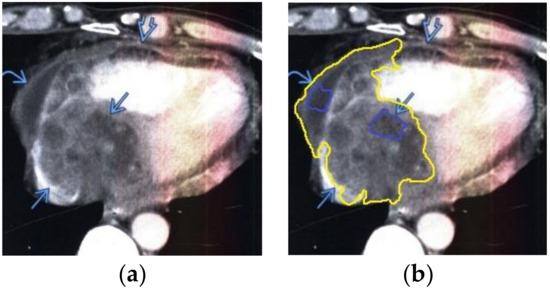

The contour extraction method was used to identify cancerous areas that, after applying the model to eliminate mixed noise, had an increased contrast of volumetric heterogeneous formations in the region of the heart [27]. This method was developed by the authors when analyzing thermal images to assess the condition of the coronary vessels of the myocardium under cardiopulmonary bypass. The contours of the cancerous regions in the examples used for applying the model to eliminate mixed noise (Figure 4, Figure 5, Figure 6, Figure 7, Figure 8 and Figure 9) are highlighted in yellow and they represent the visual boundary of the distribution of volumetric heterogeneous formations.

• For a patient with renal cell carcinoma: during MRI with contrast enhancement in the right ventricle and interventricular septum, the volumetric formation of a heterogeneous structure in the form of infiltrated metastases was determined (Figure 6).

Figure 6. Heart MRI: (a) image with white noise and (b) denoised image with contrast enhancement of volumetric heterogeneous formation in the form of metastases.